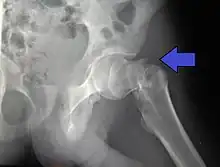

Subcapital fracture in a 92-year-old woman

X-rays of the affected hip usually make the diagnosis obvious; AP (anteroposterior) and lateral views should be obtained.